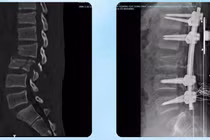

3 cuộc phẫu thuật lớn cứu nam sinh đa chấn thương nguy kịch

Khi đi làm về người bệnh gặp tai nạn nghiêm trọng trên cầu Nhật Tân trong tình trạng đa chấn thương, hôn mê sâu, được Thứ trưởng mở đường cấp cứu tới bệnh viện.